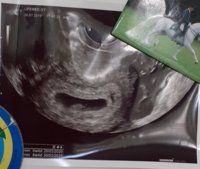

Kaikki olin hyvin pienellä tässä kohtaa. Kuten arvasin niin vastaa viikkoja 6+4 tai 6+5 vaikka neuvolan mukaan tänään olis jo 7+3. Alle viikolla kun heittää niin tuskin silti lähtevät laskettua muuttamaan. Ultrassa käyty, pieni sydän sykki ja viikkoja 7+6Kaikki hyvin. Nyt kun osais vähän hellittää näiden pelkojen kanssa

Kaikki olin hyvin pienellä tässä kohtaa. Kuten arvasin niin vastaa viikkoja 6+4 tai 6+5 vaikka neuvolan mukaan tänään olis jo 7+3. Alle viikolla kun heittää niin tuskin silti lähtevät laskettua muuttamaan.

Tänään oli varhaisultra yksityisellä, pieni sydän siellä sykki ja vastasi viikon pienempää kuin kierron mukaan laskettuna. 7+1 kun kierron mukaan olisi 8+1. Ens viikolla eka neuvola vasta, laskeekojan ne lasketun ajan nyt kumman mukaan? Päivitän la:n myöhemmin jos sitä siirretään. Kaikki siis hyvin, toivotaan vaan että pysyy tällä kertaa mukana loppuun asti..